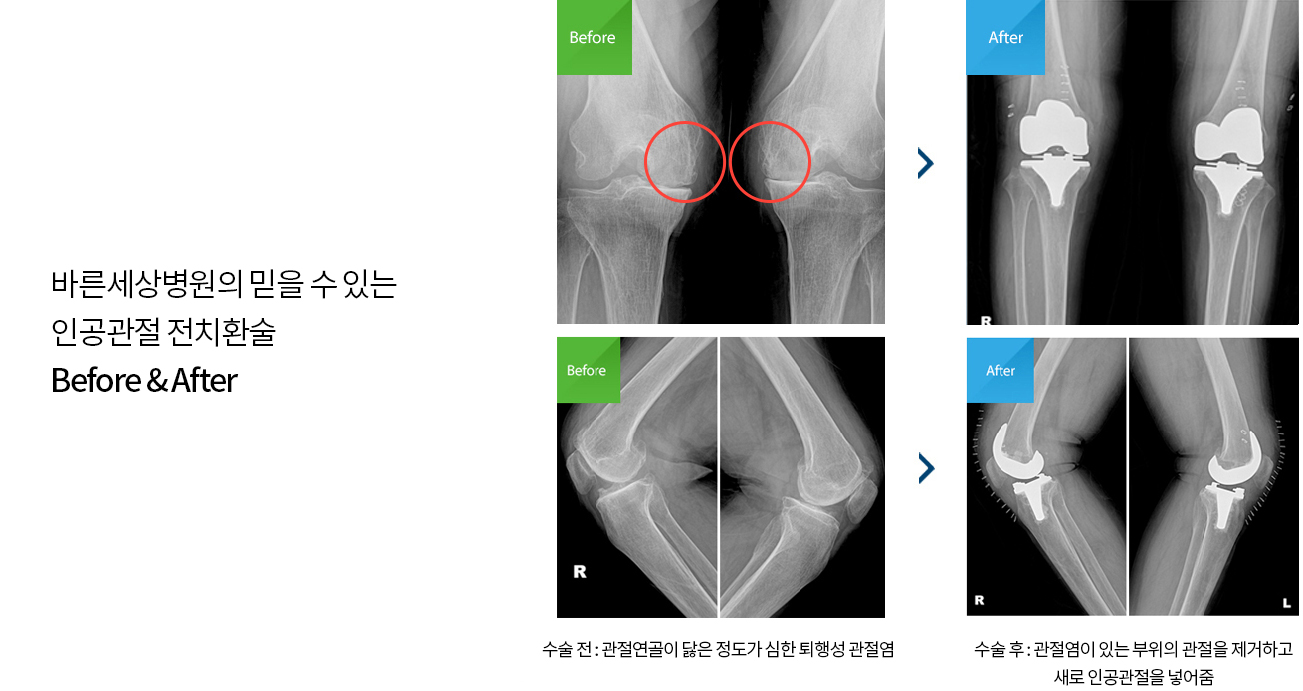

인공무릎관절 전치환술이란 연골파열이나 퇴행성 변화가 나타나 관절이 닳거나 손상되어 통증과 함께 제 기능을 하지 못할 때

손상 부위를 제거하고 특수 제작된 인공관절을 대체해주는 수술방법입니다.